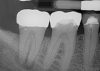

Fig 1. A preoperative radiograph was taken, the patient was administered local anesthetic, and a digital estimated measurement was recorded for initial working length.

Figure 1

A patient presented with acute pain and facial swelling. Tooth No. 6 was positive to percussion, without sensitivity to air, sweets, or temperature stimulus. Treatment options were discussed with the patient. The decision was to complete endodontic therapy to eliminate the pain (Figure 1). Definitive long-term final-restoration treatment options were presented using a fiber post and core with full-coverage CAD/CAM crown.

A smooth glide path was developed with a #15 K-file. Working length was verified with an apex locator to 29 mm.